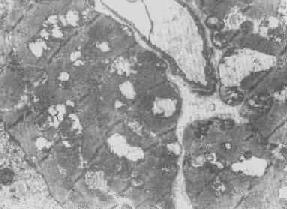

2.大小改变 细胞损伤时最常见的改变为线粒体肿大。根据线粒体的受累部位可分为基质型肿胀和嵴型肿胀二种类型,而以前者为常见。基质型肿胀时线粒体变大变圆,基质变浅、嵴变短变少甚至消失(图1-9)。在极度肿胀时,线粒体可转化为小空泡状结构(图1-10,图1-11)。此型肿胀为细胞水肿的部分改变。光学显微镜下所谓的浊肿细胞中所见的细颗粒即肿大的线粒体。嵴型肿较少见,此时的肿胀局限于嵴内隙,使扁平的嵴变成烧瓶状乃至空泡状,而基质则更显得致密。嵴型肿胀一般为可复性,但当膜的损伤加重时,可经过混合型而过渡为基质型。

线粒体肿

图1-9 线粒体肿

肾小管上皮细胞线粒体部分空泡变

图1-10肾小管上皮细胞线粒体部分空泡变

线粒体肿胀(基质型)空泡变(心肌缺氧)

图1-11 线粒体肿胀(基质型)空泡变(心肌缺氧)